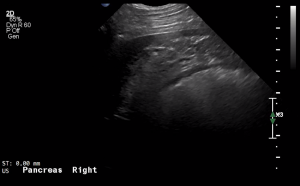

SIMON Ultrasound Database

This ultrasound database is a free resource for students and doctors!

Our collection includes videos of dogs, cats, horses, cows, humans, and many other species!

–Canine and Feline abdominal ultrasound videos were generously provided by the Cummings School of Veterinary Medicine at Tufts University.